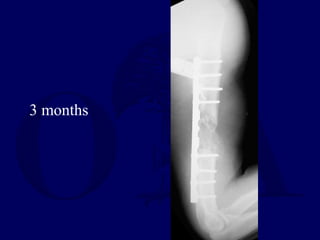

2 months

3 months

Irrigation and Debridement Applicationof external fixator Wound care Antibiotics

• 21.

Posterior plate fixation Iliaccrest bone grafting + antibiotic CaSo4 beads Implantable bone stimulator